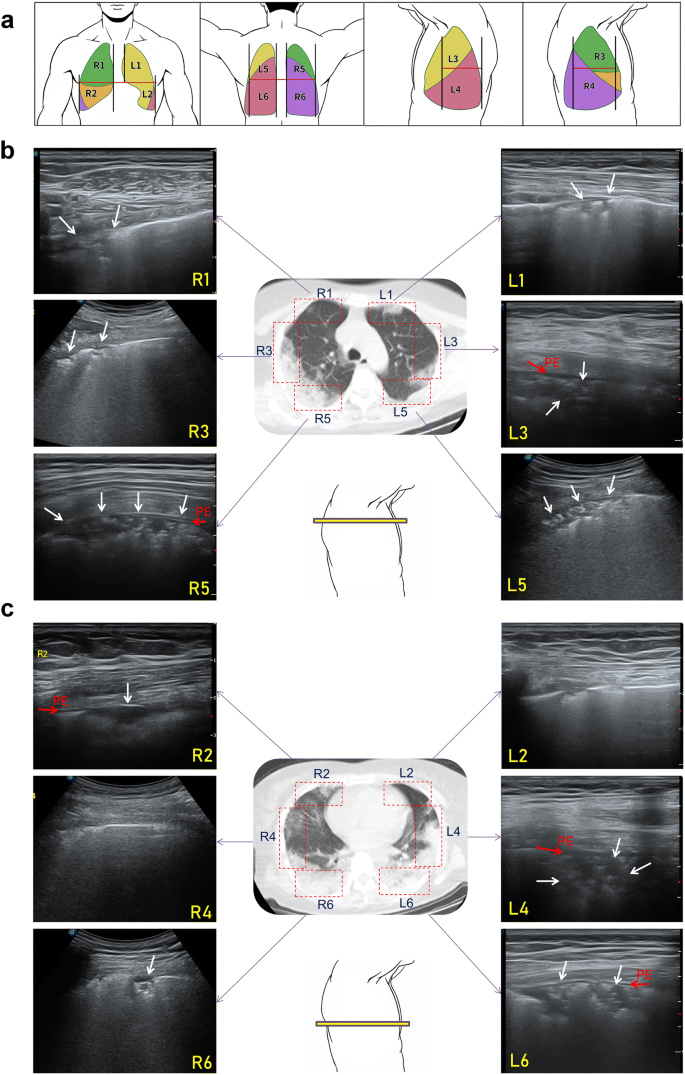

Case Report Lung Ultrasound Correlates With Low Dose Ct Scan For Early Diagnosis Of Covid 19 Axis Imaging News

Lung Ultrasonography Versus Chest Ct In Covid 19 Pneumonia A Two Centered Retrospective Comparison Study From China Springerlink